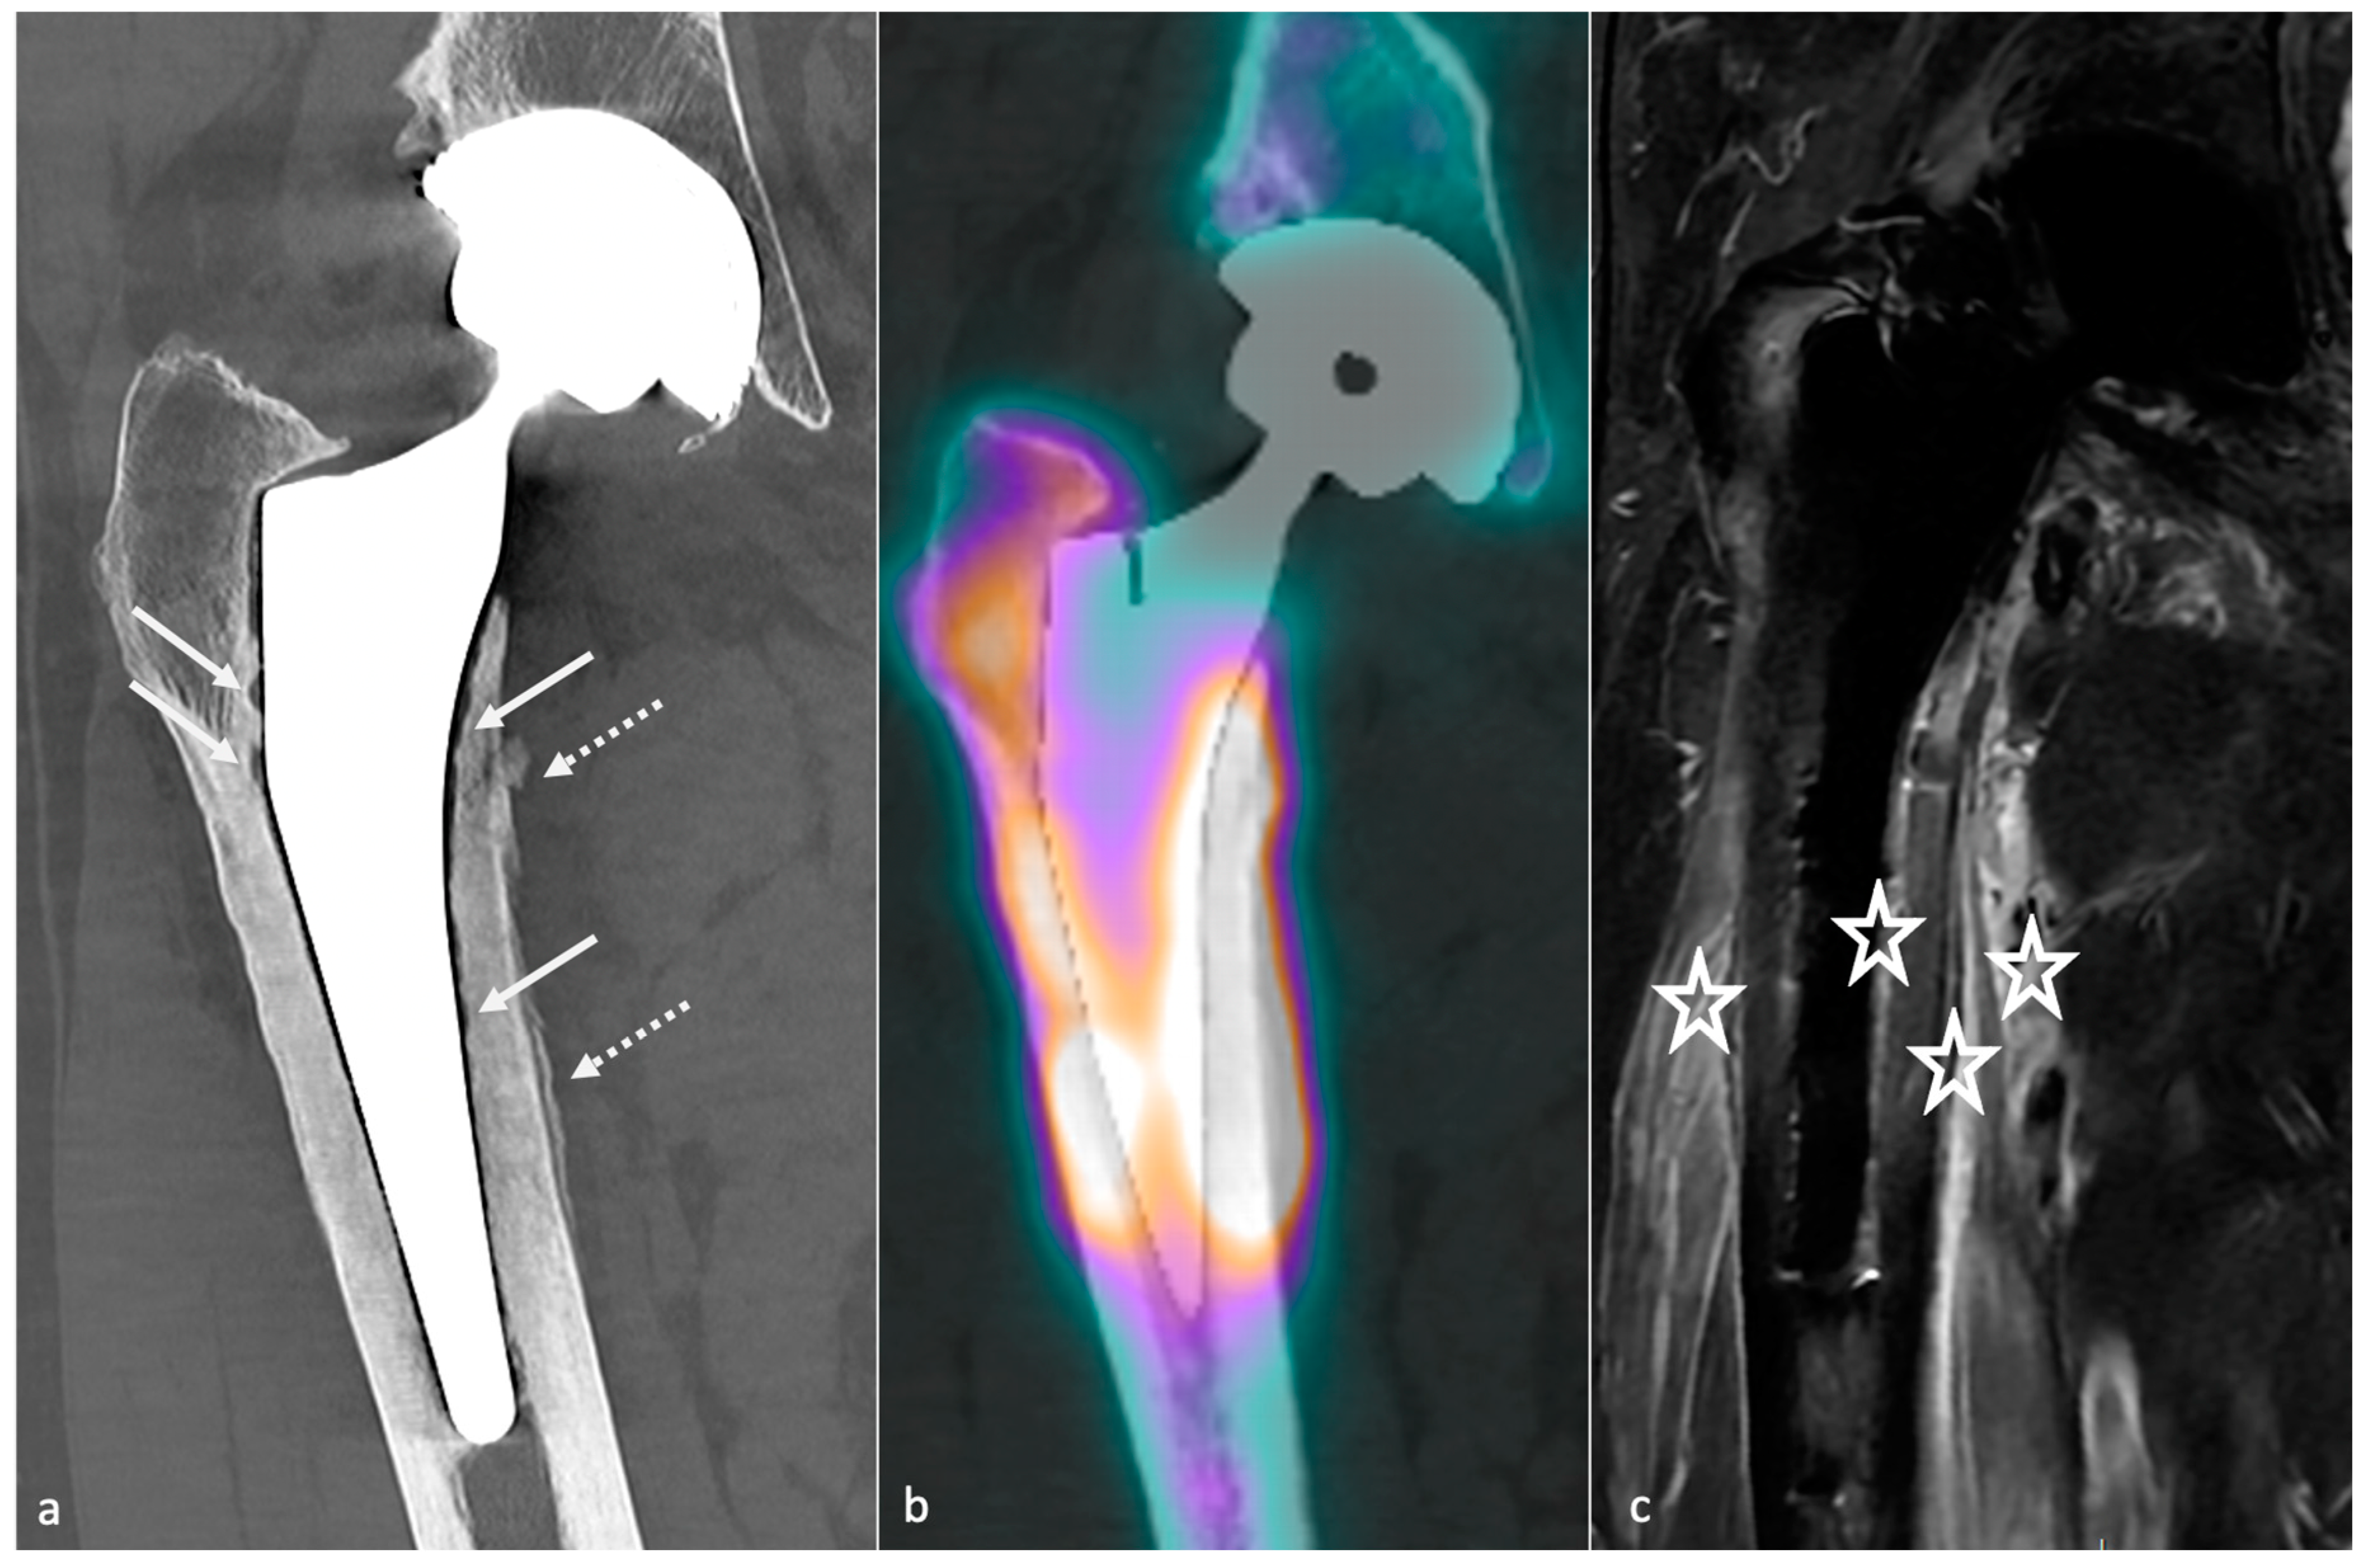

4.10. Peri-Prosthetic Fractures and Stress Reactions

4.10.1. Background

4.10.2. Imaging